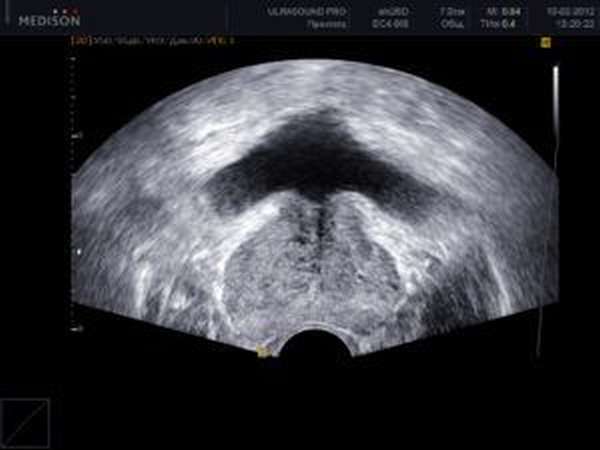

- УЗИ почек, мочевого пузыря и других органов мочеполовой системы (направлено на установление размеров и уровня сужения мочеточника),